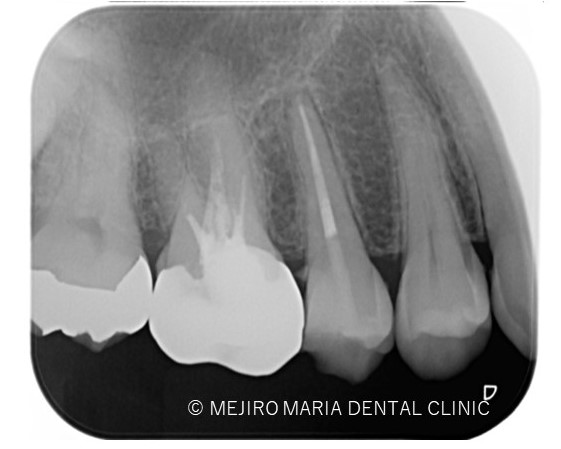

右上の歯牙を4本(右上第一小臼歯〜第二大臼歯)診査したところ、5番には明らかな根尖病変は確認ができません。

しかしながら、歯髄診断を行うと右上5番の歯髄に生活歯髄反応はみられず、歯髄壊死を起因とする根尖性歯周炎の診断に至りました。

診査の結果、右上5番の歯髄には歯髄生活反応は確認できず、歯髄壊死が起因となる根尖性歯周炎と診断しました。術前のレントゲン診査により、根尖が2つに分岐していることを確認できます。

一度見失った根管は通常の根管治療では追従が難しくなるため、感染を根管内に留めてしまう原因となります。その為、術前のレントゲン診査が非常に重要となります。